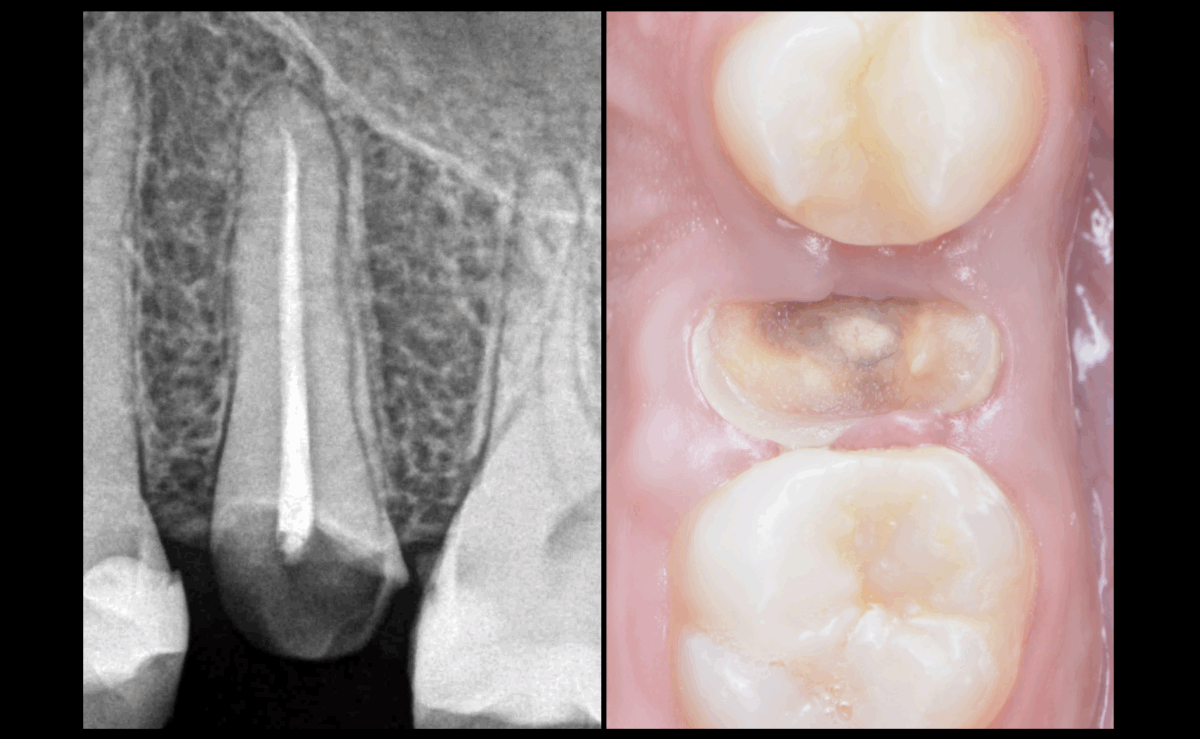

📉 Étant donné les 𝐦𝐚𝐮𝐯𝐚𝐢𝐬 𝐩𝐫𝐨𝐧𝐨𝐬𝐭𝐢𝐜𝐬 𝐛𝐢𝐨𝐦𝐞́𝐜𝐚𝐧𝐢𝐪𝐮𝐞𝐬 𝐞𝐭 𝐩𝐫𝐨𝐭𝐡𝐞́𝐭𝐢𝐪𝐮𝐞𝐬 de cette 25, considérons qu’elle soit à extraire.

Oui, l’élongation coronaire ou l’extrusion chirurgicale/orthodontique pourrait être envisageable…

➡️ Mais considérons qu’elle soit à extraire.